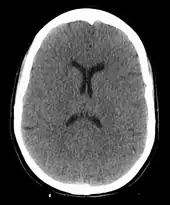

Anoxic brain injury following a hanging. The loss of grey white matter differentiation and small ventricles due to brain swelling are visible.

A hanging may induce one or more of the following medical conditions, some leading to death:

The cause of death in hanging depends on the conditions related to the event. When the body is released from a relatively high position, the major cause of death is severe trauma to the upper cervical spine. The injuries produced are highly variable. One study showed that only a small minority of a series of judicial hangings produced fractures to the cervical spine (6 out of 34 cases studied), with half of these fractures (3 out of 34) being the classic "hangman's fracture" (bilateral fractures of the pars interarticularis of the C2 vertebra).[24] The location of the knot of the hanging rope is a major factor in determining the mechanics of cervical spine injury, with a submental knot (hangman's knot under the chin) being the only location capable of producing the sudden, straightforward hyperextension injury that causes the classic "hangman's fracture".